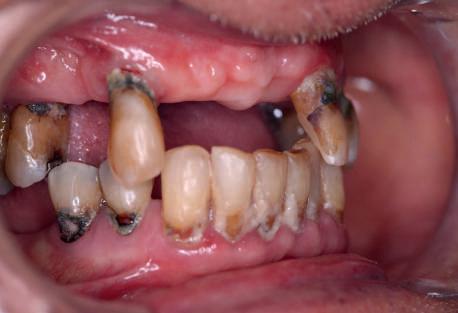

60 year old male patient visits the clinic with the desire to restore his oral health in a fully comprehensive manner.

Upon physical examination we found absence of teeth in both jaws and remaining teeth with recurrent caries, advanced periodontal disease and mobility; with a poor prognosis for function and aesthetics. We proceeded to take all the preparatory records such as: scans, photographs, x-rays, tomography and other diagnostic elements for the planning of rehabilitation by means of dental implants.